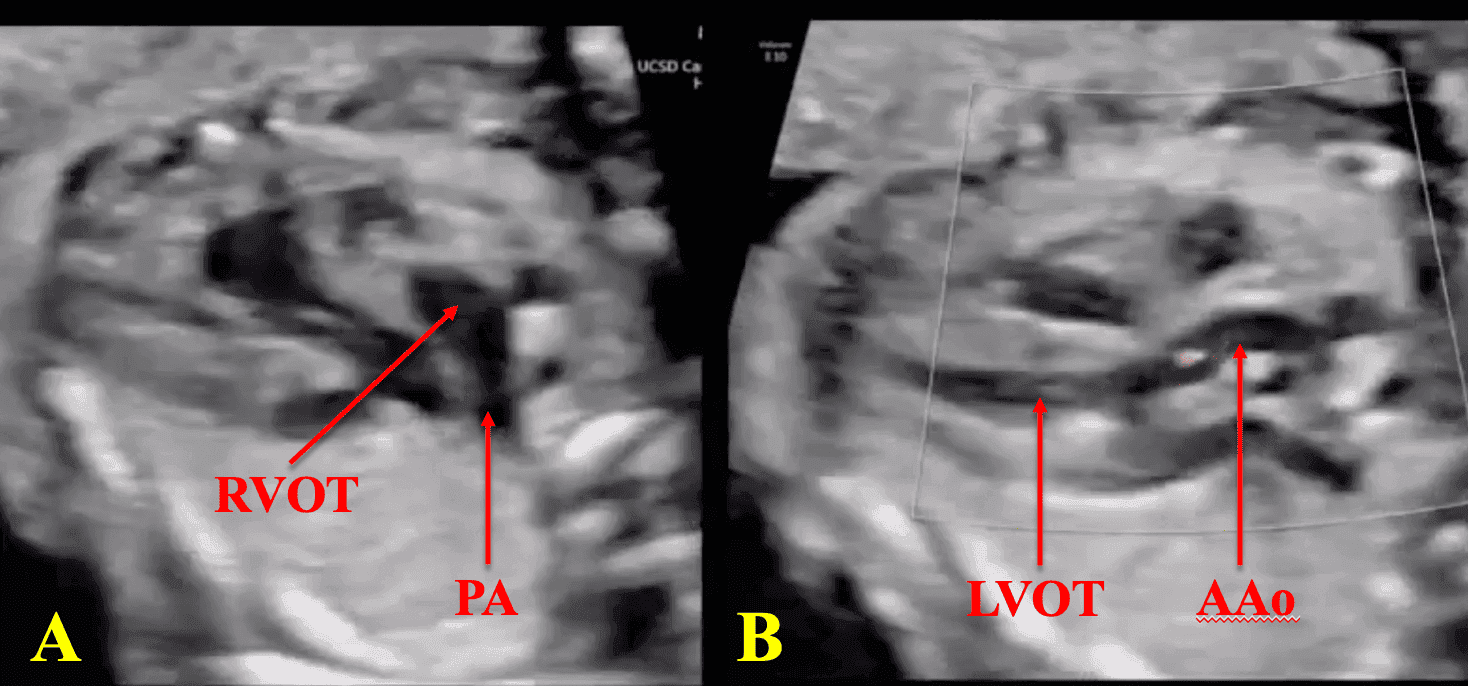

This course provides an in-depth understanding of fetal cardiac outflow tract anatomy and anomalies, focusing on conditions such as Tetralogy of Fallot, Transposition of the Great Arteries, and Double-Outlet Right Ventricle. Participants will learn how to accurately assess the fetal heart using advanced ultrasound techniques like the three-vessel trachea (3VT), three-vessel view (3VV), and left ventricular outflow tract (LVOT) views. Emphasizing the importance of early detection, this course will cover key methods for identifying ductal-dependent lesions and other critical outflow tract defects. By completing this course, clinicians will be equipped to improve prenatal diagnosis, enhance neonatal outcomes, and optimize surgical planning for congenital heart disease (CHD).